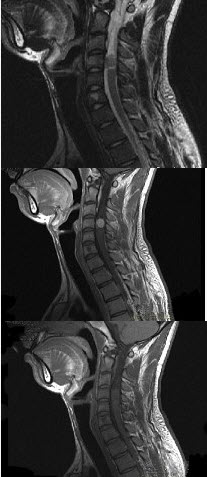

男,24岁,颈部疼痛,并右上肢麻木,以手部明显,请根据所提供图像,选择最可能的诊断()。

A、颈4~5)神经鞘瘤

B、颈4~5)脊膜瘤

C、颈4~5)海绵状血管瘤

D、颈4~5)血管母细胞瘤

E、颈4~5)胶质瘤

A